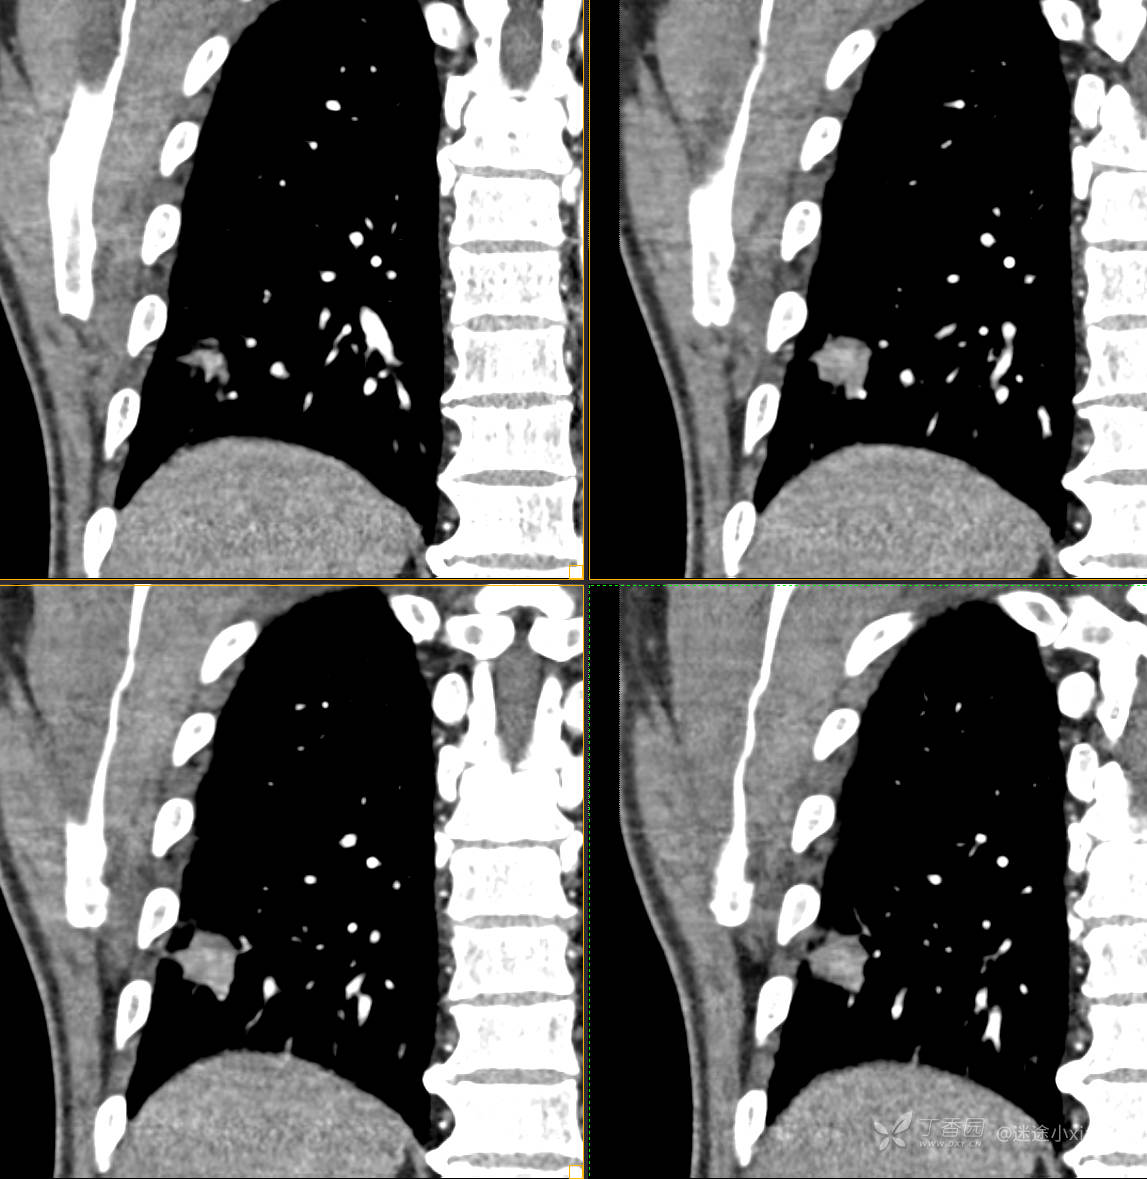

胸组50:老年男性,发现肺占位一天,(结果公布)

主诉: 发现右肺占位1天

现病史: 患者诉1日前在当地医院检查时胸部CT示;肺结节(具体不详),当时无胸闷气急。 无咳嗽咳痰,无胸痛,无恶心呕吐等。今为求进一步治疗,门诊拟“肺结节”收治入院。病来,患者神志清,精神可,胃纳睡眠可,二便无殊,体重无明显增减。